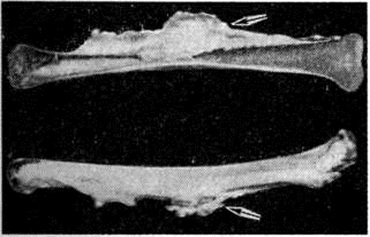

Макроскопически патологический процесс имеет вид костного утолщения (гиперостоза), которое при локализации на длинных трубчатых костях (бедренная, большеберцовая, плечевая) как бы стекает сверху вниз с образованием характерных напластований, напоминающих наплывы горящей свечи (рисунок 1).

Рис. 1.

Макропрепарат распила большеберцовой кости при мелореостозе: плотные костные наслоения кортикального слоя, напоминающие наплывы свечи, указаны стрелками (вверху — вид со стороны распила, внизу — вид снаружи).